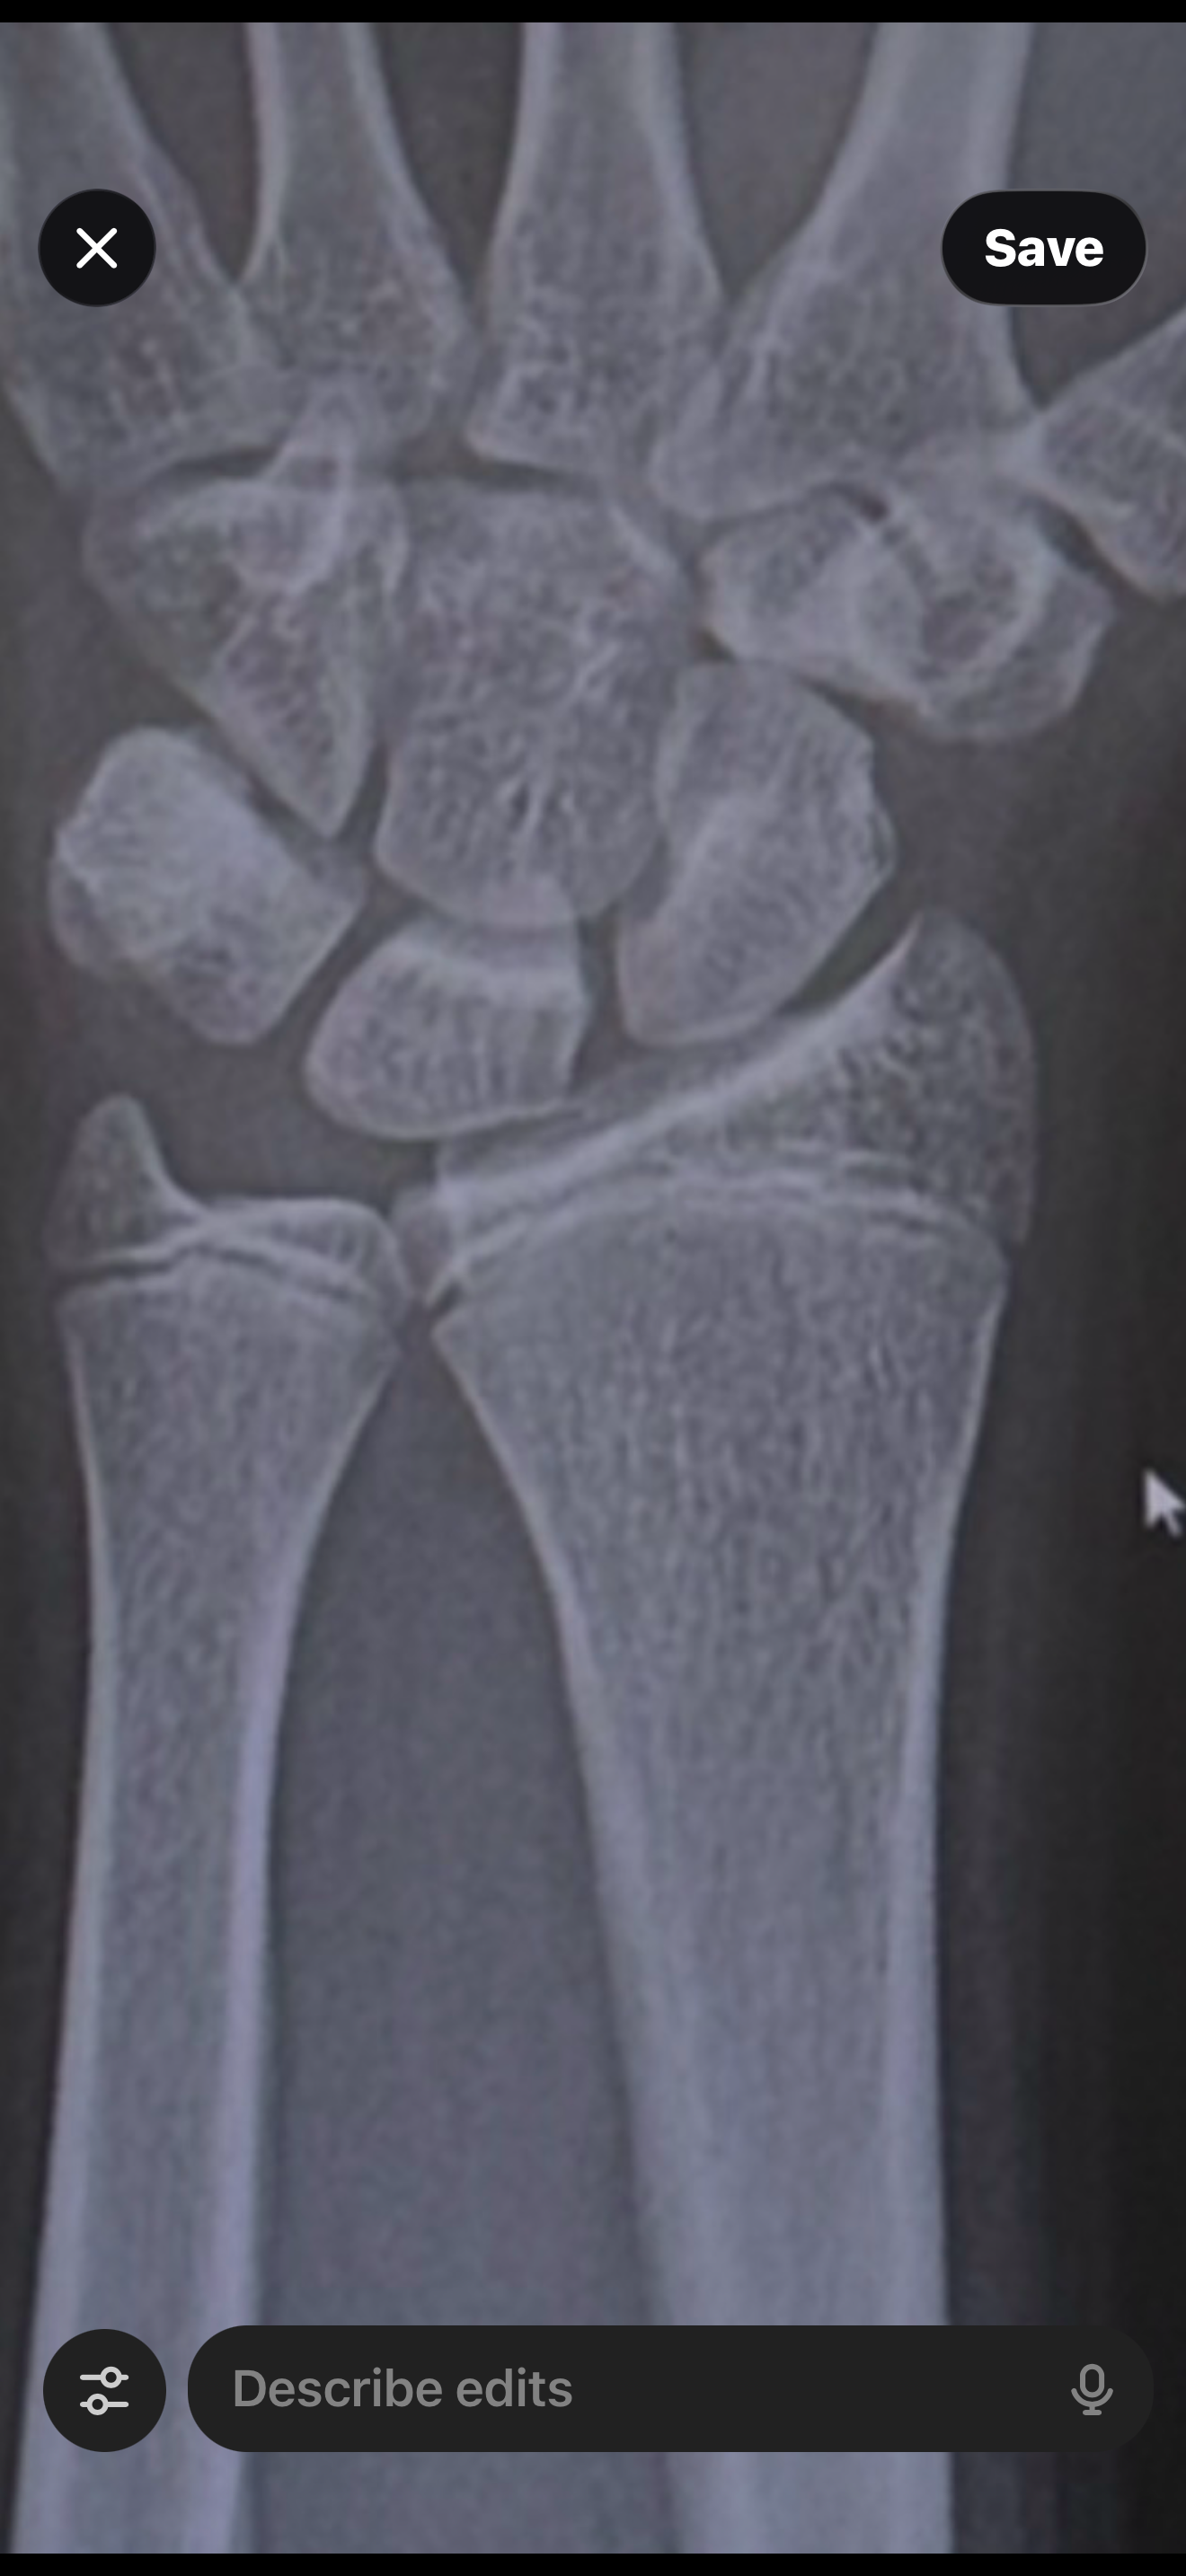

Here is a better pic

View attachment 4852437

U still got VERY little left

0.3-0.5 inch left

But i doubt it would be significant so I accepted my height